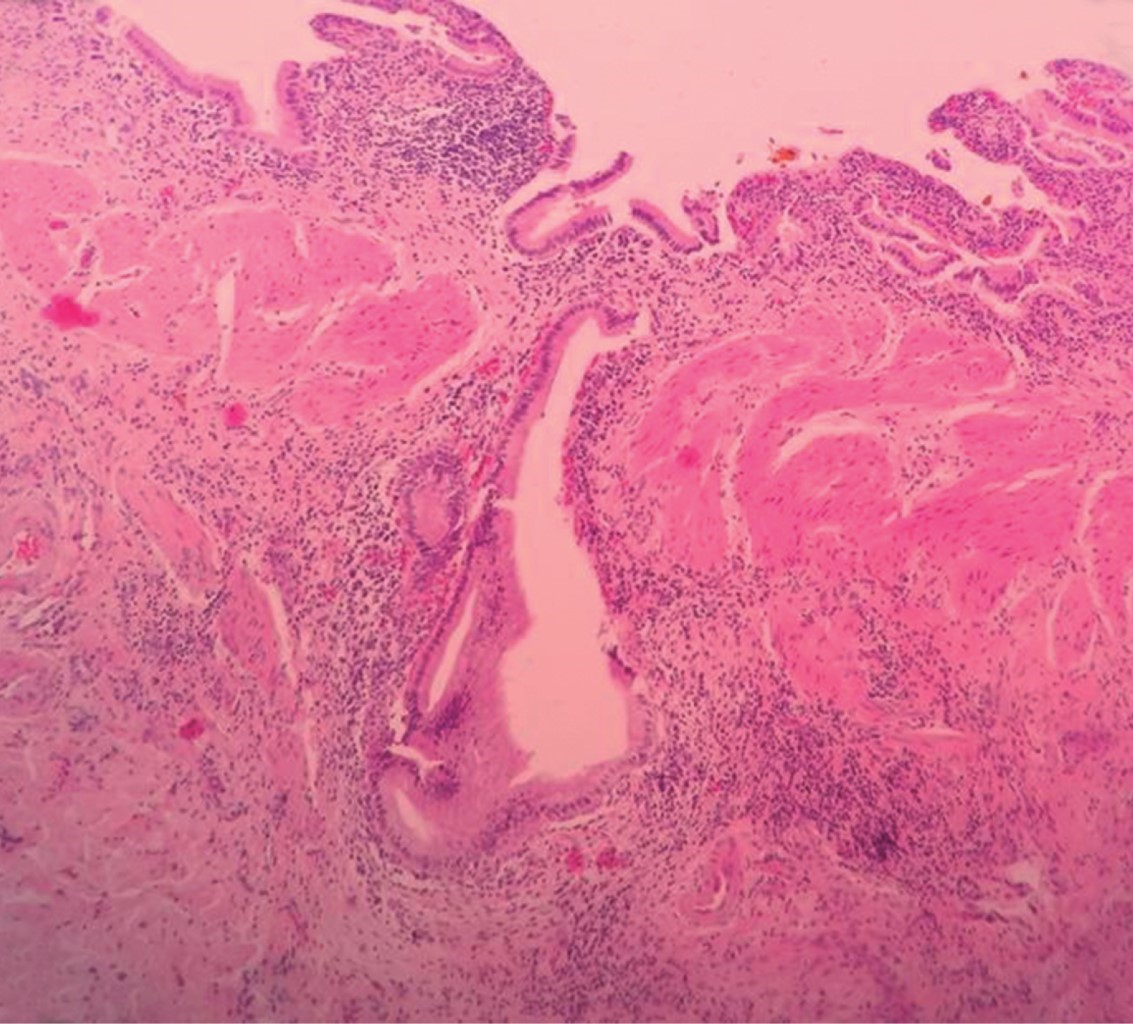

La ADM/VB predomina en adultos mayores de 50 años. Este estudio muestra una media etaria mayor (65.7 años), así como el hallazgo entre 1 y 9%3 de las piezas de colecistectomías, siendo en esta serie mucho menor (0.07%). En este reporte la incidencia de litiasis vesicular asociada (38.4 %) se ajusta a la literatura que muestra una incidencia entre 36 y 95%.4 En la patogenia de la ADM/VB se postulan mecanismos inflamatorios y mecánicos. La asociación entre cálculos vesiculares y los cambios inflamatorios crónicos que producen, sugieren que el crecimiento epitelial es estimulado por la inflamación permanente,5 aunque también se postula que la excesiva absorción de bilis a nivel de la pared vesicular genera inflamación que estimula el crecimiento epitelial. Otros orígenes de la inflamación parietal han sido citados, por ejemplo, reflujo pancreático/vesicular crónico, especialmente en pacientes con implantación anormal del Wirsung a nivel del colédoco.6,7 Además, las alteraciones en la motilidad vesicular por hiperactividad neuromuscular incrementan la presión intraluminal, empujan el epitelio hacia la capa muscular y producen su diverticulización, formando los senos de Rokitansky-Aschoff (senos RA) (Figura 1).8

Figura 1